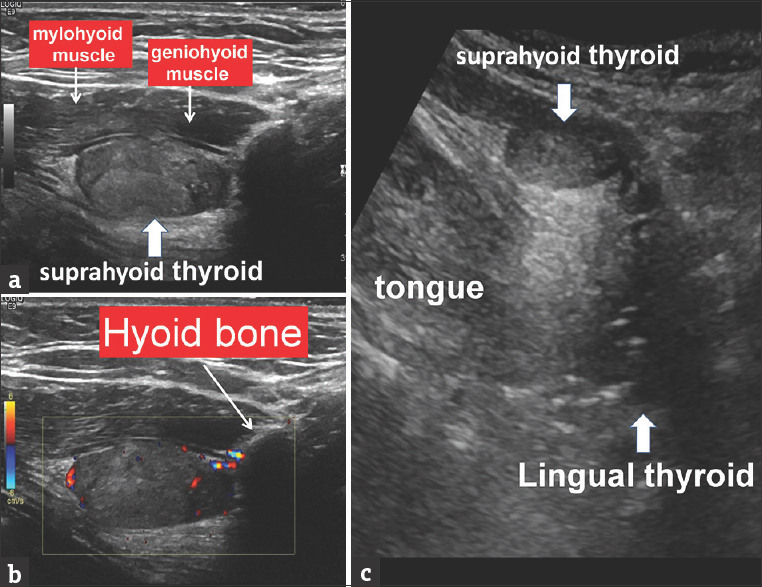

Figure, Ectopic thyroid] - StatPearls - NCBI Bookshelf Ectopic Thyroid - Endocrinesurgery.net.au Sites of ectopic thyroid localization along its descending pathway. | Download Scientific Diagram Ectopic thyroid tissue in the head and neck: a case series | BMC Research Notes | Full Text | Ectopic Thyroid